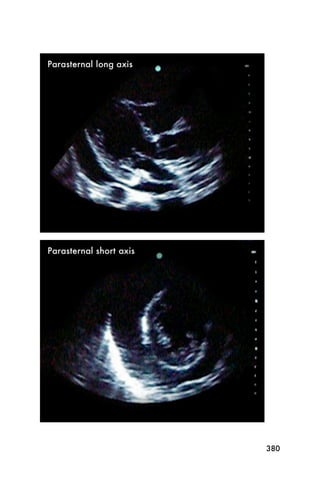

Parasternal long axis

Conventionally, for adult patients, the parasternal long

axis view is performed first in the exam. This view is

extremely useful. The patient should be placed on their

left side. The probe is placed to the left of the patient s

sternum, in the area of the 3rd to 5th rib space, as

shown in Figure 1.

Figure 1. Probe position for parasternal long axis view. The arrow

Parasternal short axis view

The parasternal short axis view uses the same area on

the patient s chest as the parasternal long axis view. The

probe is turned clockwise 90 degrees so the probe

marker is pointing near the patient s left shoulder, as

shown in Figure 9.

89

Figure 9. Probe position for parasternal short axis view. The probe

marker (arrow) points toward the left shoulder

The left ventricle should look round like a circle, and

the right ventricle usually looks like a C attached to

the side of the left ventricle. See Figure 10 for an

example of the ultrasound image from parasternal short

axis position.